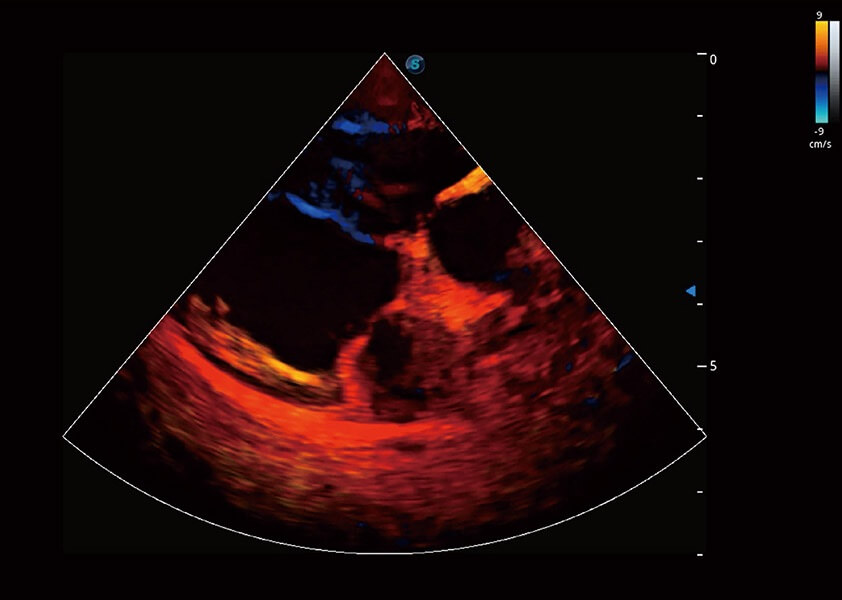

ProPet 60 作为一款高端台式动物超声设备,为动物医生的日常诊断提供了一系列贴合动物临床需求、解决临床实际问题的高级成像功能。凭借全系列高清探头,满足医生对腹部、心脏、生殖、浅表、肌骨等成像的所有需求,切实帮助您提升检查效率,提高诊断信心。

动物是人类最亲密的朋友和最值得信赖的伙伴。MILE米乐集团官网也一直致力于探索动物专用的超声影像解决方案。 全新推出的ProPet系列,是MILE米乐集团官网在动物超声影像智能化、专业化、精准化的一次跨越式革新。动物不能用言语来表述自己的不适,通过超声影像,ProPet系列搭建了动物医生与不同物种沟通的“桥梁”,为动物医生注入了“治愈之力”。